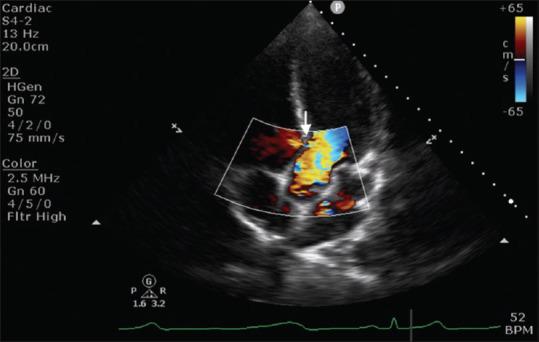

经食管超声心动图在原位肝移植中的应用:一篇叙述性综述。

Utility of transesophageal echocardiography during orthotopic liver transplantation: A narrative review.

Orthotopic liver transplantation (OLT) is the standard of care for patients suffering from end stage liver disease (ESLD). This is a high-risk procedure with the potential for hemorrhage, large shifts in preload and afterload, and release of vasoactive mediators that can have profound effects on hemodynamic equilibrium. In addition, patients with ESLD can have preexisting coronary artery disease, cirrhotic cardiomyopathy, porto-pulomary hypertension and imbalanced coagulation. As cardiovascular involvement is invariable and patient are at an appreciable risk of intraoperative cardiac arrest, Trans esophageal echocardiography (TEE) is increasingly becoming a routinely utilized monitor during OLT in patients without contraindications to its use. A comprehensive TEE assessment performed by trained operators provides a wealth of information on baseline cardiac function, while a focused study specific for the ESLD patients can help in prompt diagnosis and treatment of critical events. Future studies utilizing TEE will eventually optimize examination safety, quality, permit patient risk stratification, provide intraoperative guidance, and allow for evaluation of graft vasculature.

原位肝移植(OLT)是治疗终末期肝病(ESLD)患者的标准方法。这是一种高风险的手术,可能会导致出血、前负荷和后负荷的大幅变化,以及血管活性介质的释放,这些都会对血液动力学平衡产生深远影响。此外,ESLD 患者可能存在先前存在的冠状动脉疾病、肝硬化性心肌病、门肺高压和凝血失衡。由于心血管受累是不可避免的,并且患者在术中心脏骤停的风险相当大,因此在没有使用 TEE 禁忌的情况下,TEE 越来越成为 OLT 期间常规使用的监测手段。由经过培训的操作人员进行的全面 TEE 评估提供了大量关于基线心脏功能的信息,而针对 ESLD 患者的重点研究有助于快速诊断和治疗危急事件。未来使用 TEE 的研究最终将优化检查的安全性、质量,允许患者进行风险分层,提供术中指导,并评估移植物血管。